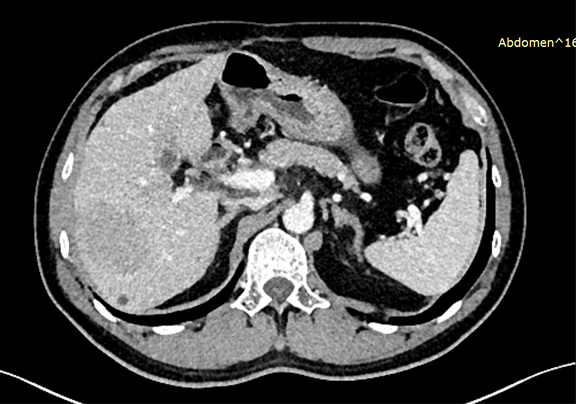

下腹部增强CT示:符合肝脏术后改变,请结合临床;肝右叶占位性病变,考虑肝Ca 可能性大。

将0.625mm双源薄层CT资料的静脉期和动脉期Dicom格式文件导入海信CAS系统。

通过调节窗宽窗位调整CT序号,对肿瘤,肝实质,胆囊,下腔静脉,肿瘤,肝动脉、门静脉及肝静脉等进行三维重建;系统自动计算肿瘤体积和肝脏体积。

术前CT检查:

动脉期

静脉期